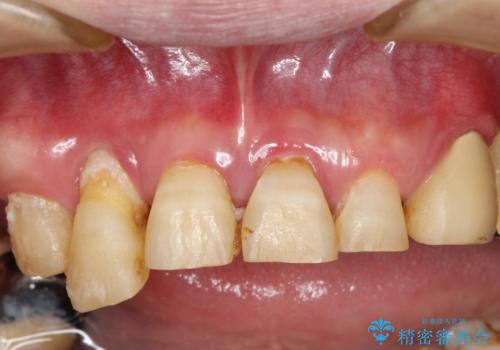

虫歯だらけ、歯周病 崩壊した口腔の再建 フルマウスリコンストラクション

様々な治療手段を高いレベルで同時に併行して行うことが必要でした。

費用・時間は多大にかかりましたが、今後しっかりと咬んで生活することができるでしょう。